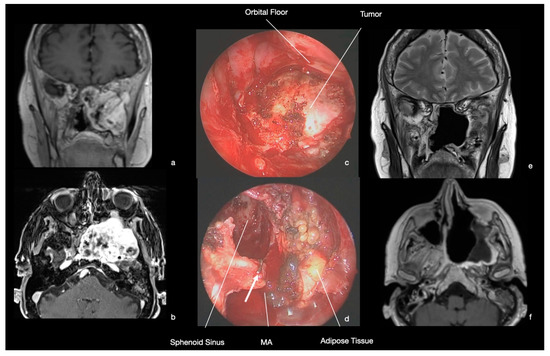

9.1. Case 1